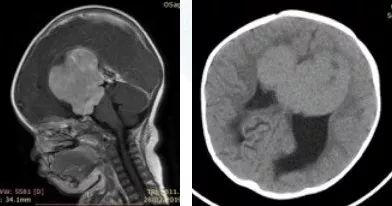

一岁小朋友巨大视神经胶质瘤,三名国际教授连夜提供第二意见

“肿瘤位置极深,孩子年龄太小,脑瘤太大,手术风险很高,切除率不高,且术后极大可能出现失明……”辗转托付熟人朋友挂专家号,问诊过很多国内大医院的神经外科医生,得到的说法如出一撤。

小晴父母发动了身边的亲朋好友寻找国外的儿童神经外科专家,最终得知INC国际神经外科医生集团旗下世界神经外科顾问团中有三位世界神经外科领域赫赫有名的儿童神经外科专家——德国巴特朗菲教授、意大利Concezio Di Rocco教授、加拿大James T.Rutka教授,于是快速取得与INC国际神经外科医生集团中国代表处的联系,并整理小晴的所有影像报告、病例资料等同时与这三位儿科教授进行了远程咨询。由于孩子病情紧急,在INC国际神经外科医生集团的努力协调下,三位国际教授连夜给出了国际水准的咨询意见。

INC三位海外儿童神外专家在看过小晴的情况后,得出了总体上比较一致的咨询建议——患儿很可能为鞍区视神经胶质瘤,这通常是低级别或良性肿瘤,且治愈率较高。这种低级别胶质瘤治疗方法是完全彻底地手术切除,这对于解除大脑的局部压力非常重要,但同样也要面临手术所承担的风险,包括垂体功能不全、视力障碍和中风等。如果能够最大程度安全切除,则预后生存率会非常好,不会干扰正常的生活,后续持续跟踪及接受适当的治疗,则可与一般人寿命相似,但对于复发率的评估需要根据肿瘤的级别及性质决定。

对于手术切除程度,INC三位海外儿科专家都有着比较明确的评估,一般都能达到80%以上的切除率,在这方面巴特朗菲教授在他的一系列临床病例中证明了⼤量全切/次全切除的可能性与良好的功能结果有关。手术过程中的风险与肿瘤的⾎管特征有关,因为婴⼉年龄很⼩,血液储备有限,这需要仔细的⿇醉处理、极为熟练的手术团队配合,也需要术中磁共振成像系统(iMRI)、术中神经电生理监测、术中神经导航等设备护航。